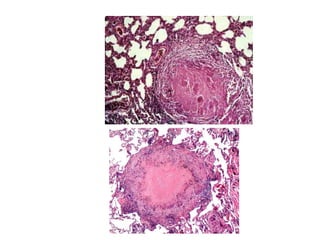

Tubercle

Avascular granuloma composed of

 a caseous necrosis in a central area

 encircled by a zone of epitheloid cells,

 a peripheral zone of lymphocytes, granulocytes and

fibroblasts. –multinucleated giant cells

 Calcification may be present in the necrotic centers.

 An outer boundary of fibrous tissue is usually present

between the lesions and normal tissue.

Tubercle Avascular granuloma composedof  a caseous necrosis in a central area  encircled by a zone of epitheloid cells,  a peripheral zone of lymphocytes, granulocytes and fibroblasts. –multinucleated giant cells  Calcification may be present in the necrotic centers.  An outer boundary of fibrous tissue is usually present between the lesions and normal tissue.